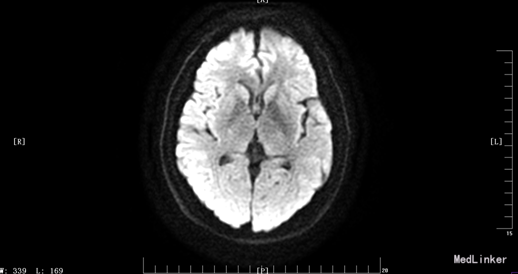

入院体检:T 36.9°C,P 87次/分,R 22次/分,BP 136/69mmHg。全身皮肤无黄染及出血点,全身浅表淋巴结未扪及肿大。双肺呼吸音清,未闻及干湿性罗音。心率87bpm,律齐,各瓣膜听诊区未闻及杂音。腹平,腹肌软,肝脾肋下未及,无压痛、反跳痛,肠鸣音正常。脊柱四肢无畸形,双下肢无水肿。神经系统:神清语晰,对答切题,记忆力、定向力、计算力正常,查体合作。双侧瞳孔等圆等大,直径约3mm,对光反射灵敏,双眼球活动自如,未见眼震。双侧额纹对称,双侧鼻唇沟对称,伸舌居中。四肢肌张力正常,左侧肢体肌力II级,指鼻试验、跟膝胫试验、闭目难立征未能配合检查。双侧腱反射对称存在,双侧巴氏征未引出。颈软,双侧克氏征、布氏征(-)。 辅助检查:生化:超敏C反应蛋白:2.6mg /l、乳酸脱氢酶(LDH):105U/L、甘油三酯(TG):2.32mmol/L、尿酸(URIC):416umol/L;同型半胱氨酸:14.3umol /l;D-二聚体定量:270ng /ml;糖化血红蛋白(HbA1c):5.1%;红细胞沉降率:3mm/h;人脂蛋白相关磷脂酶A2:378ng /ml;风湿十二项:(-); 胸部DR:主动脉硬化,双肺未见异常。心脏彩超:LVEF:66%。心内结构未见异常。 心内未见异常血流。 左室舒张功能降低。颈血管彩超:双侧颈总动脉、颈内动脉、颈外动脉、椎动脉未见异常。 双侧颈动脉、椎动脉血流速度正常。 急诊CT未见明显异常。 头颅MR:1、 双侧额叶软化灶,病灶周边少许胶质增生;2、MRA示未见明显异常。 头颅CTA:双侧颈内动脉虹吸段、双侧大脑中动脉、双侧大脑前动脉及其分支管壁尚规则,管腔通畅未见明显狭窄;右侧椎动脉颅内段管腔较左侧稍细小,余椎动脉、基底动脉及双侧大脑后动脉管腔未见明显变窄。大脑willis动脉环清晰显示,未见明显异常。 头颅CTV:大脑静脉系统上矢状窦、窦汇、横窦、乙状窦、直窦、大脑大静脉和颈内静脉管壁规则,管腔通畅未见狭窄、畸形等异常。 动态心电图示:1.窦性心动过缓;2.偶发室性早搏;3.偶发房性早搏;4.提示不完全性右束支阻滞;5.T波改变(心率快时);6.心率变异性:正常。 脑电图无异常。

患者入院时血压不高,溶栓后立即行头颅MR,未见明显病灶。但患者体征尚存在,考虑可行头颅的薄层扫描或者改变B值。另外关于栓子的来源还有疑惑,颈动脉超声没看到动脉硬化、板块,TCD结果也正常。后来再回顾病史,患者发病的过程中有感到心慌,急诊生化血钾稍低,动态心电图报有窦性心动过缓、不完全性右束支阻滞,可考虑为心源性。另患者入院时出现左手抖动、头痛症状,为刺激性症状,但MR、CTA、CTV、脑电图未见异常。也是一个疑惑的地方,希望大家给予交流指正。患者一周后出院,左侧肢体肌力几乎恢复正常。